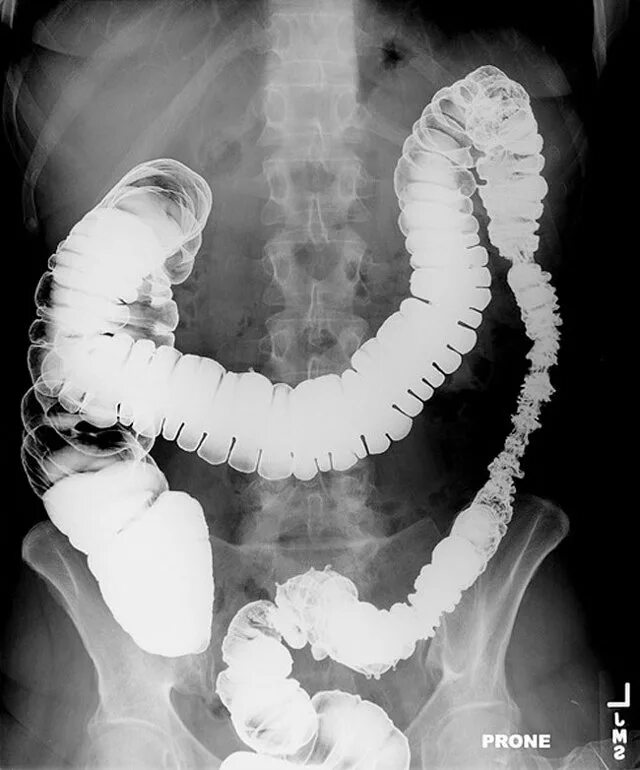

Рентгеноскопия жкт